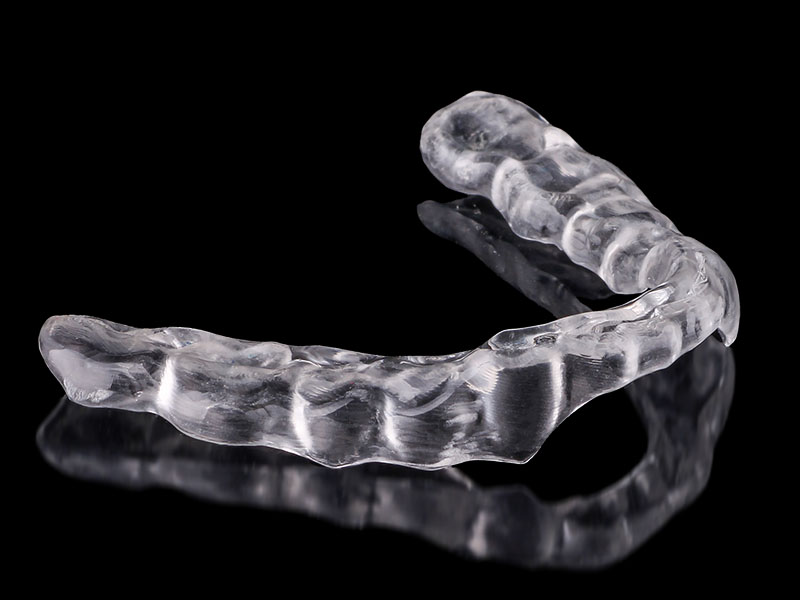

Szyna, którą wykonujemy, to precyzyjna orteza – projektowana cyfrowo, dopasowana do pozycji spoczynkowej żuchwy, zaprojektowana na podstawie rejestracji, skanów i badania funkcjonalnego.

3. Frezowanie i oddanie szyny

Szyna jest wycinana z akrylu DD Bio Splint P HI. Oddawana z pełną analizą

kontaktów, prowadzeń i wygody.